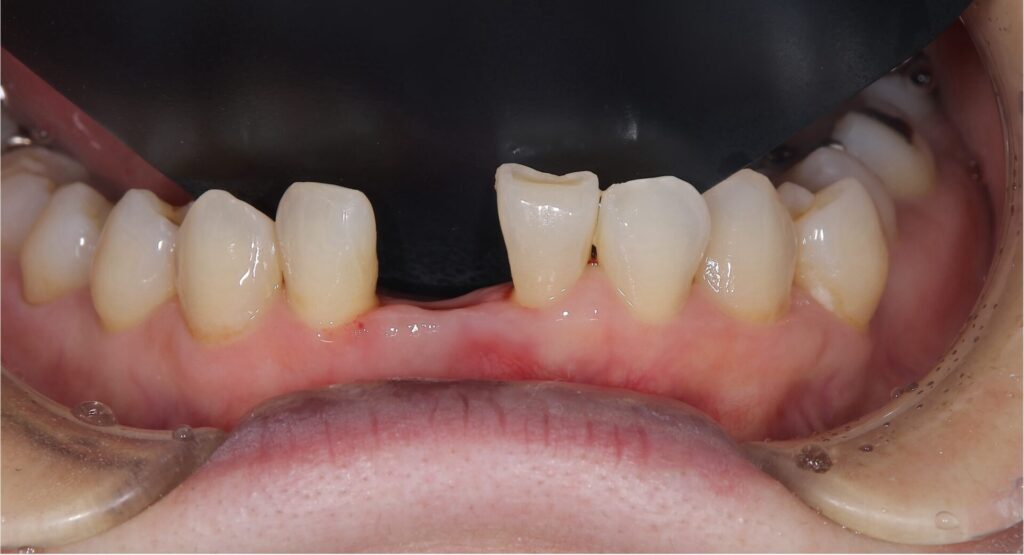

今回の患者様は右下の前歯(向かって真ん中左の歯)が歯周病が進行してしまい抜歯と判断いたしました

抜歯を行うだけだと歯茎の退縮が生じてしまうため、歯茎が退縮しないように考慮しながら抜歯を行いました

この状態から、歯の欠損部に接着ブリッジを作製していきました